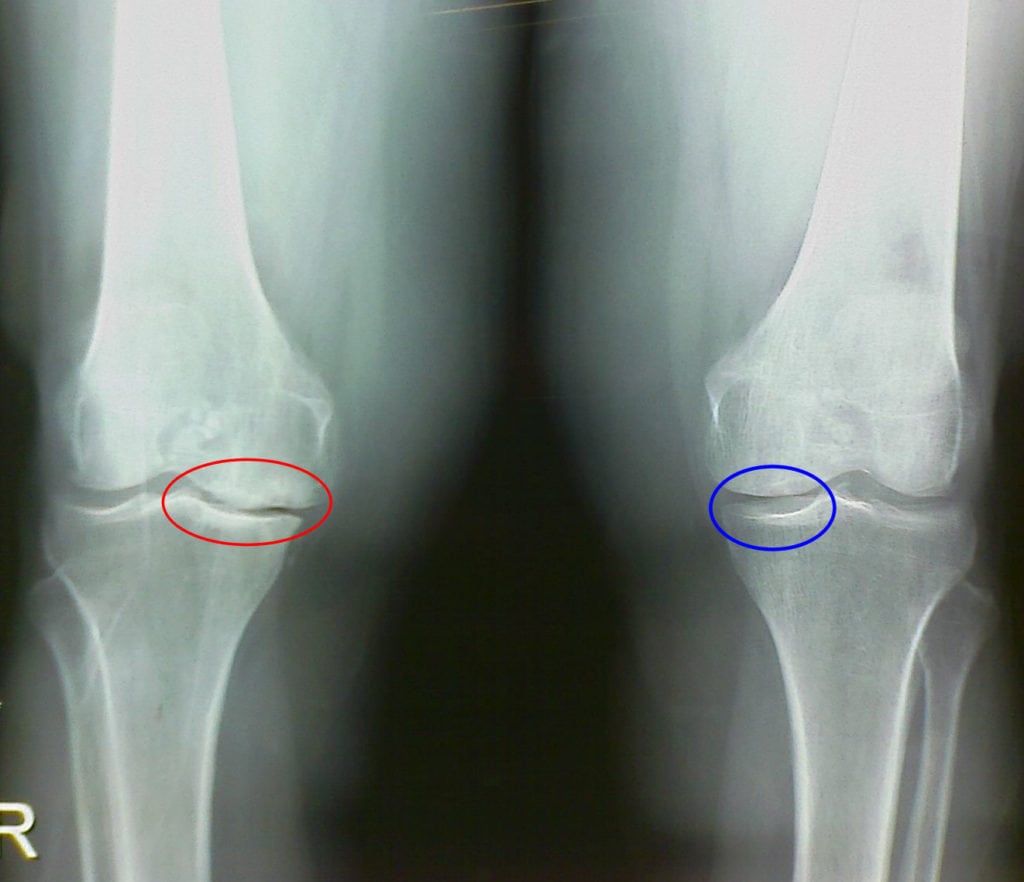

Здоровый коленный сустав – это прекрасно отлаженная биологическая машина, в которой механические движения осуществляются за счет четкой балансировки процессов различной природы. Одна из ведущих ролей принадлежит биохимическим процессам, в частности, процессы разрушения и синтеза суставного хряща идут с одинаковыми скоростями. Если в результате каких-то причин это равновесие нарушается, процесс разрушения может стать основным. Наблюдаются дистрофические и дегенеративные процессы в тканях хряща, что сопровождается сильными болями, нарушением двигательной функции, а в дальнейшем может привести к его разрушению и деформации сустава. Это заболевание называется артрозом.

Для лечения этого состояния необходимы вещества, способные защитить и восстановить разрушенные суставные хрящи. Такие вещества существуют и называются хондропротекторами. По статистике наиболее часто артроз поражает коленный сустав. Далее в статье речь пойдет о том, как используются хондропротекторы при артрозе коленного сустава.

На сегодняшний день наибольшее распространение в лечебной практике получили хондропротекторы для суставов второго поколения. Их применение имеет некоторые особенности. Лечение остеоартроза коленного сустава (гонартроза) хондропротекторами имеет максимальную эффективность на 1 или 2 стадиях артроза, если же сустав уже деформирован или хрящ полностью разрушен, хондропротекторы не помогут. При остеоартрозе коленного сустава человек обращается к врачу в состоянии, когда коленный сустав сильно болит при ходьбе и в покое, может отекать. В это время основная задача – как можно быстрее избавить пациента от боли, обеспечив ему приемлемое качество жизни. В такой ситуации хондропротекторы не помогут, поскольку при всех их замечательных достоинствах скорость воздействия не является их сильной стороной. В острой фазе артроза часто назначают нестероидные противовоспалительные препараты: